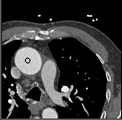

Samples for ascending aorta detection (black circle):

Cluster of candidate points in the ascending aorta.